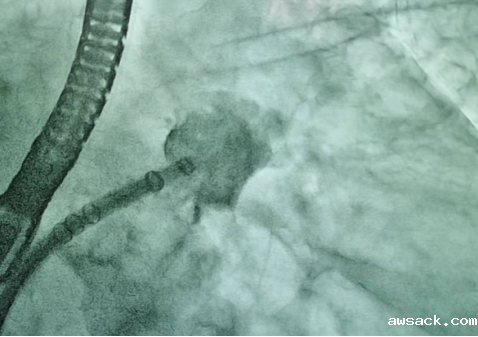

封堵后左心耳造影